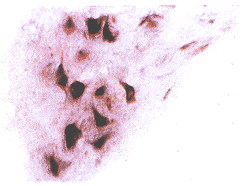

正常组、对照组T7~8灰质神经元胞浆内可见淡紫蓝色阳性颗粒。前角Ⅸ区大多极神经元胞浆内着色较深。后角Ⅰ~Ⅲ区未见阳性细胞。Ⅳ~Ⅵ区及中央管周围Ⅹ区见中等量杂交阳性神经元。在非神经元细胞,包括胶质细胞和星形细胞,未见阳性信号。白质中无着色。灰质中偶见阳性血管内皮细胞表达。见图1,2。损伤组T7~8灰质中ET-1 mRNA表达明显增多,主要表现为数目增多,着色变深。非神经元细胞及白质中未见阳性表达,后角Ⅰ~Ⅲ区见少量阳性细胞表达。损伤后0.5 h即有明显表达增多,主要表现在前角(Ⅸ区)。见图3,4。经统计学处理,前角阳性颗粒灰度和面积与对照组比较有显著性差异(P<0.05)。见表1。损伤后4 h ET-1 mRNA表达达高峰(P<0.01),48 h仍有明显升高(P<0.05),至72 h趋于正常水平。正常组与对照组比较无明显差异。

图3 损伤4 h,大鼠T8~9 ET-1 mRNA原位杂交结果 碱性磷酸酶法染色3.3×10

图4 损伤4 h,大鼠T8~9前角ET-1 mRNA原位杂交结果 碱性磷酸酶法染色3.3×40